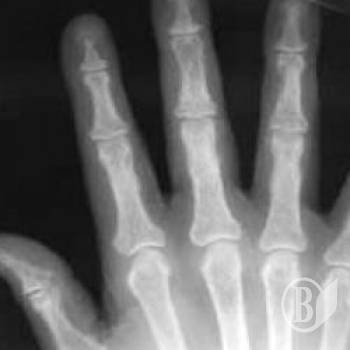

До міліції звернулася 70-річна чернігівка. Вона повідомила що її син, який проживає з нею, завдав їй тілесних ушкоджень у вигляді перелому всіх пальців правої руки.

За результатами судово-медичної експертизи такі ушкодження належать до середнього ступеня тяжкості.